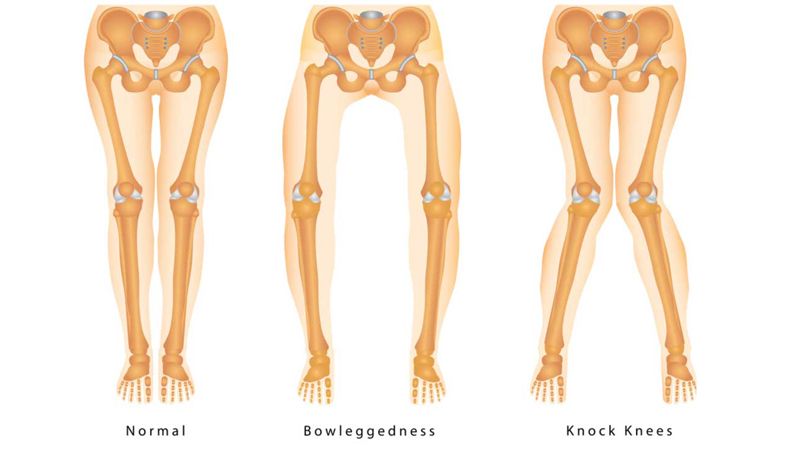

Diseases of destruction of joint surfaces

Brackets and legs

Disorder centered on limb placement or poor limb placement while walking